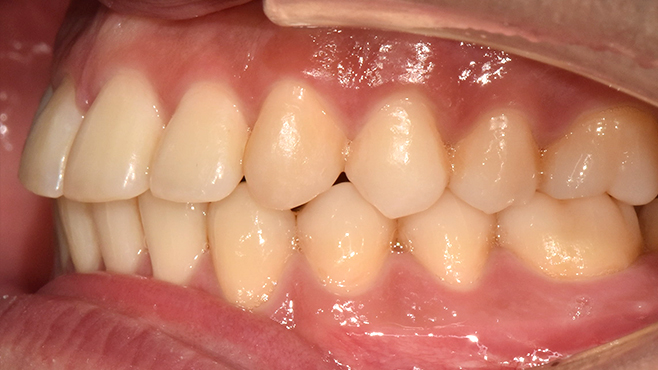

맞는 건 괜찮은데… 충치는 못 참겠습니다|20대 격투기 선수 치과 방문기